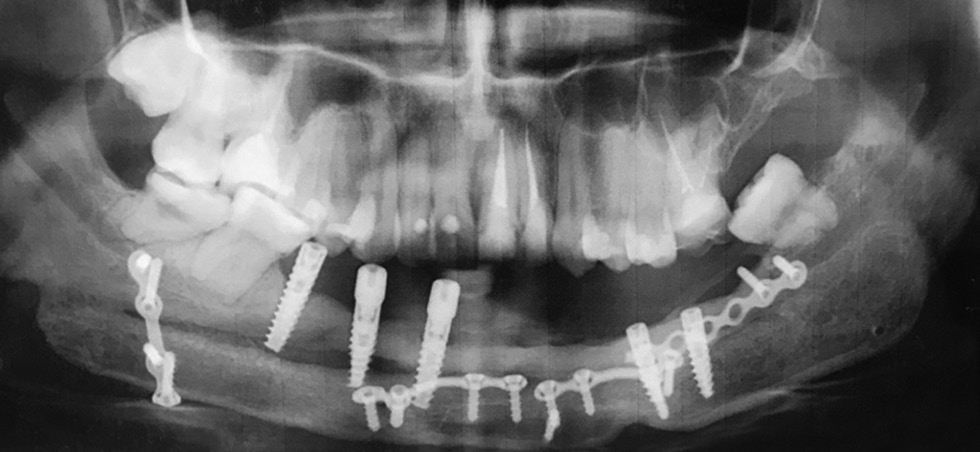

At age 21 (2018), the patient underwent the next stage of rehabilitation. Five screw implants (Hi-Tek LGI line) were installed in positions 43, 44, 45, 33, and 34 of the teeth for a bar structure and fixation of a conditionally removable denture on it. Gum tissues were grafted in positions 33 and 34 of the dental implants with a free connective tissue flap (graft) from the hard palate mucosa. The wounds were sutured with 6-0 Prolene (Fig. 9).

Fig. 9. Patient B (23 years old). After dental implantation

In September 2020, the mobility of implant 45 was revealed; it was removed, and the bed was filled with Parasorb osteogenic material. Figure 10 presents the appearance and condition of the oral cavity. The patient had no complaints about functional and esthetic disorders of the lower limb.

Fig. 10. Patient B (24 years old). Before the final stage of dental prosthetics: a, appearance; b, oral cavity state; c, X-ray image; d, lower limbs after fibular graft harvesting 7 years ago

In 2021, dental implantation in areas 45 and 35 with missing teeth was planned, followed by the manufacture of fixed dentures on six implants. The surgery was postponed because of the patient’s pregnancy.